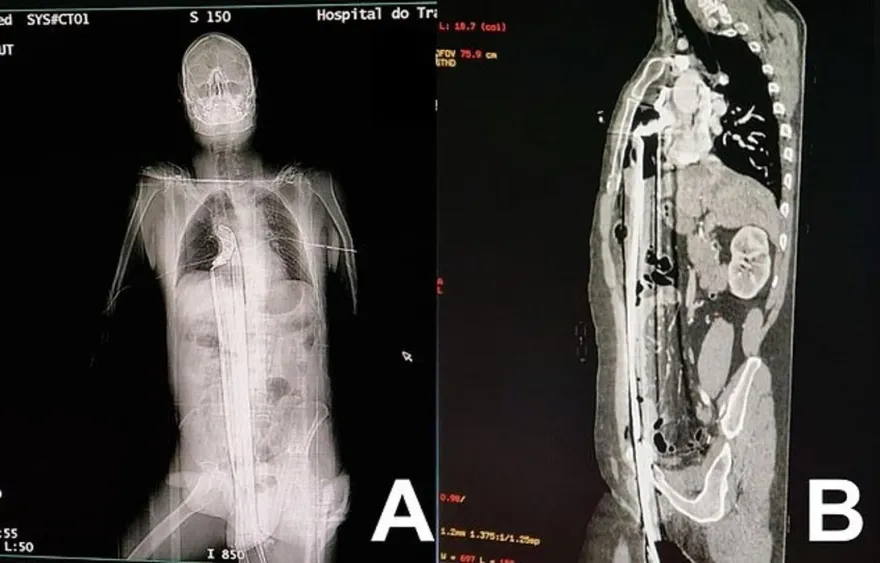

肺部

心臟

肛門

巴西